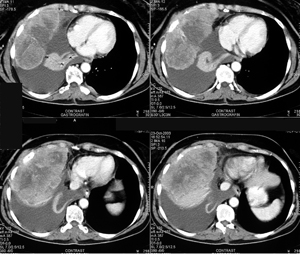

Περίπτωση Νο 3

Εικόνα 1

Αξονική τομογραφία θώρακος. Διακρίνεται ευμεγέθης όγκος του θωρακικού τοιχώματος με υπεζωκοτική συλλογή που προκαλεί ατελεκτασία του κάτω λοβού του δεξιού πνεύμονος.